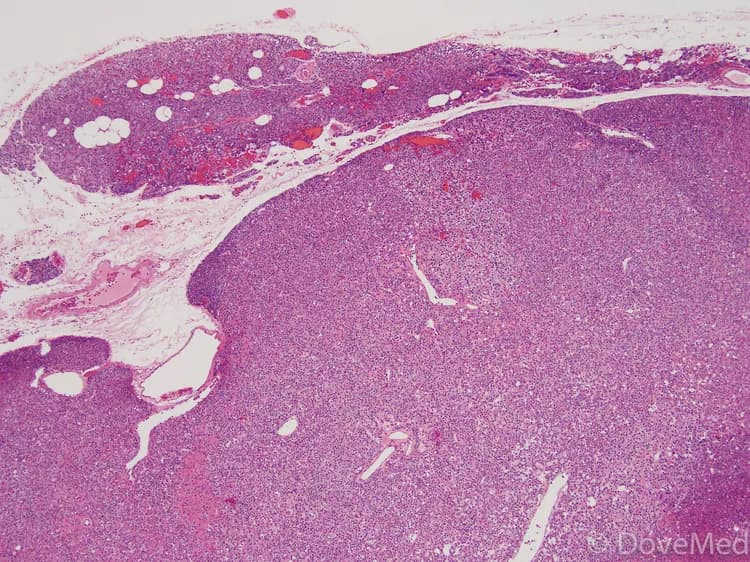

What happens to tissue (if any), taken out during the Procedure?

The tissue is taken for further examination and later archived or disposed, as per the standard protocols in the treating hospital.

When should you expect results from the pathologist regarding tissue taken out, during the Procedure?

• The tissue removed is processed in the laboratory under a pathologist's supervision

• Slide(s) are prepared once the tissue is processed and is examined by a pathologist and a pathology report issued

• Depending on the complexity of the case, issue of the report may take anywhere between 72 hours to a week's time